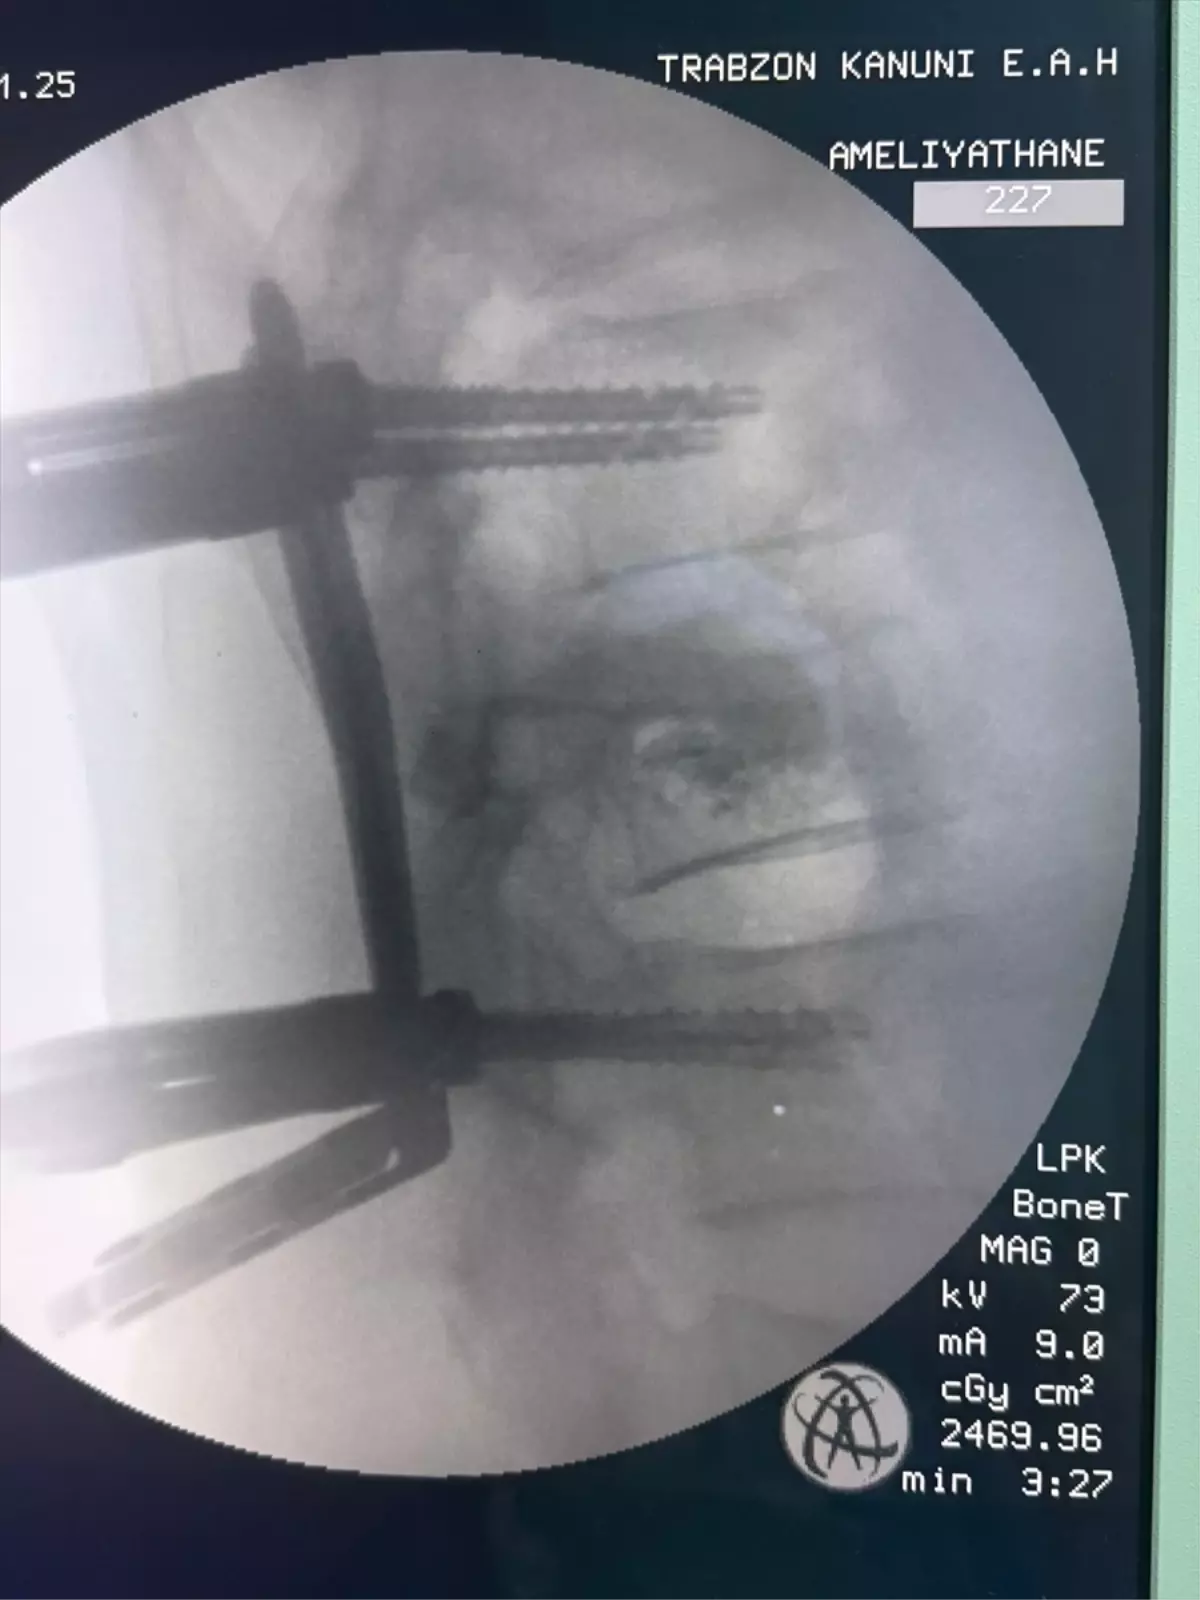

Kanuni Eğitim ve Araştırma Hastanesi'nde gerçekleştirilen omurga vidalama ameliyatı sayesinde hasta...